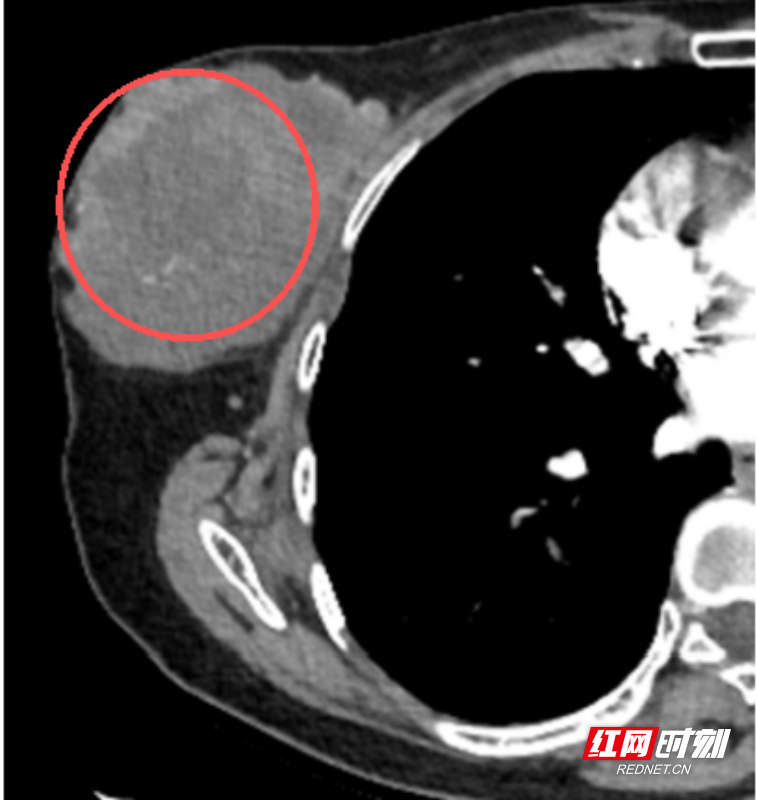

患者谢某(化名)一年前无意中触摸到右侧乳房有一小肿块,因不痛不痒,便未予重视。然而近三个月来,肿块迅速增大,就诊时已长成直径约10厘米,导致乳房严重变形,生活深受影响。来到郴州市第四人民医院心胸乳腺外科就诊,经过紧急穿刺活检,确诊为“乳腺叶状肿瘤”。

直径约10厘米的肿块。

由于肿瘤体积巨大,几乎替代了正常腺体,且表面皮肤已出现水肿,为彻底切除病灶、避免复发,医疗团队经慎重评估,为患者施行了右侧乳房全切术。术后病理证实为交界性叶状肿瘤,切缘干净。目前患者恢复良好,已康复出院。她追悔道:“总以为不疼就没事,要是早一年来筛查,结果可能完全不同。”